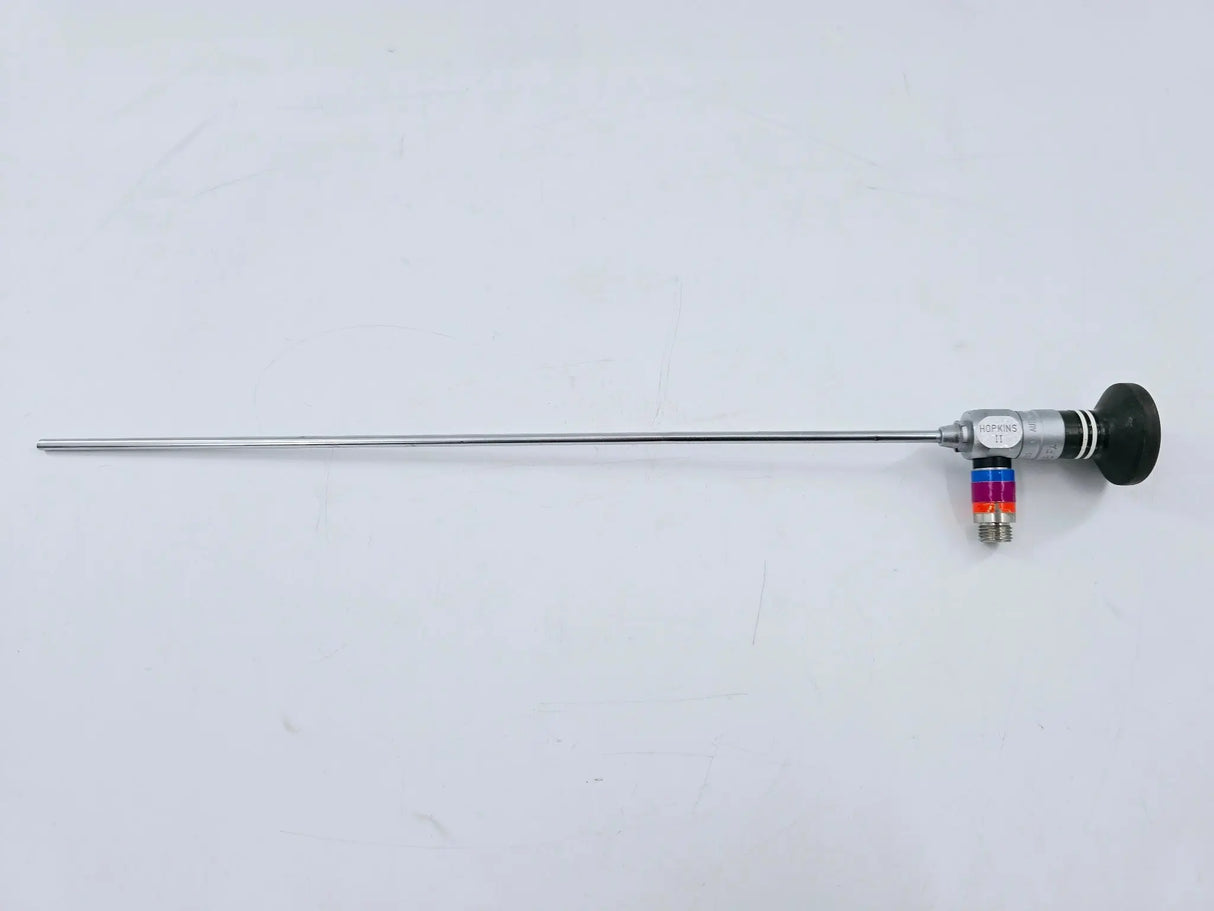

Karl Storz 27005FA Hopkins Rigid Optical Cystourethroscope 12°, 4mm x 30cm 14"

Karl Storz 27005FA Hopkins Rigid Optical Autoclavable Cystourethroscope 12°, 4mm x 30cm Urology 14"

• Model: 27005FA

• 12-Degree, 4mm x 30cm Shaft

• Overall Length: 14 inches

These surgical instruments are categorized as limited use and are in excellent condition. They may be new out of the original manufacturer's packaging or have similar characteristics indicative of minimal prior use. Despite their limited usage, they maintain an exceptional quality suitable for medical procedures.